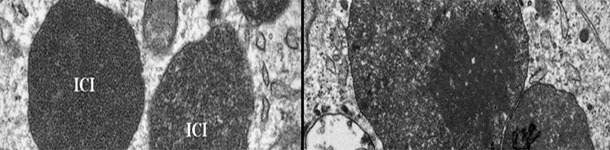

Seit kurzem geht man davon aus, dass PCV2 ein Krankheitserreger ist, der bei Schweinen Diarrhö auslöst, und es wurde vorgeschlagen, die PCV2-Darmerkrankung (PCV2-ED) als eigenes Krankheitsbild innerhalb der Erkrankungen, die durch porcine Circoviren induziert werden (PCVDs), zu betrachten.